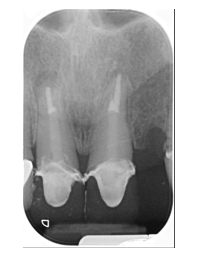

What is a pontic?

Pontic: An artificial tooth on a fixed dental prosthesis that replaces a missing natural tooth, restores its function, and usually fills the space previously occupied by the clinical crown

What is a modified ridge lap pontic?

A pontic design that is the most common type.

contact with ridge buccaly

What is an ovate pontic?

A pontic design requiring soft tissue surgery, mostly used for anterior teeth.

Q

A

A pontic design that allows space for cleaning underneath.

no contact with ridge at all